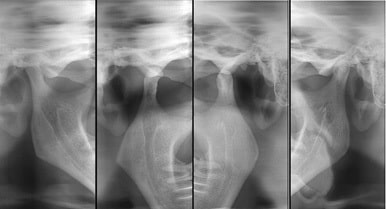

ATM

A ATM (articulação temporomandibular) é a articulação da mandíbula com o crânio e, nela, é possível observar os componentes ósseos envolvidos.

Um exame que pode ser realizado de três maneiras: com a boca aberta, fechada e em repouso.